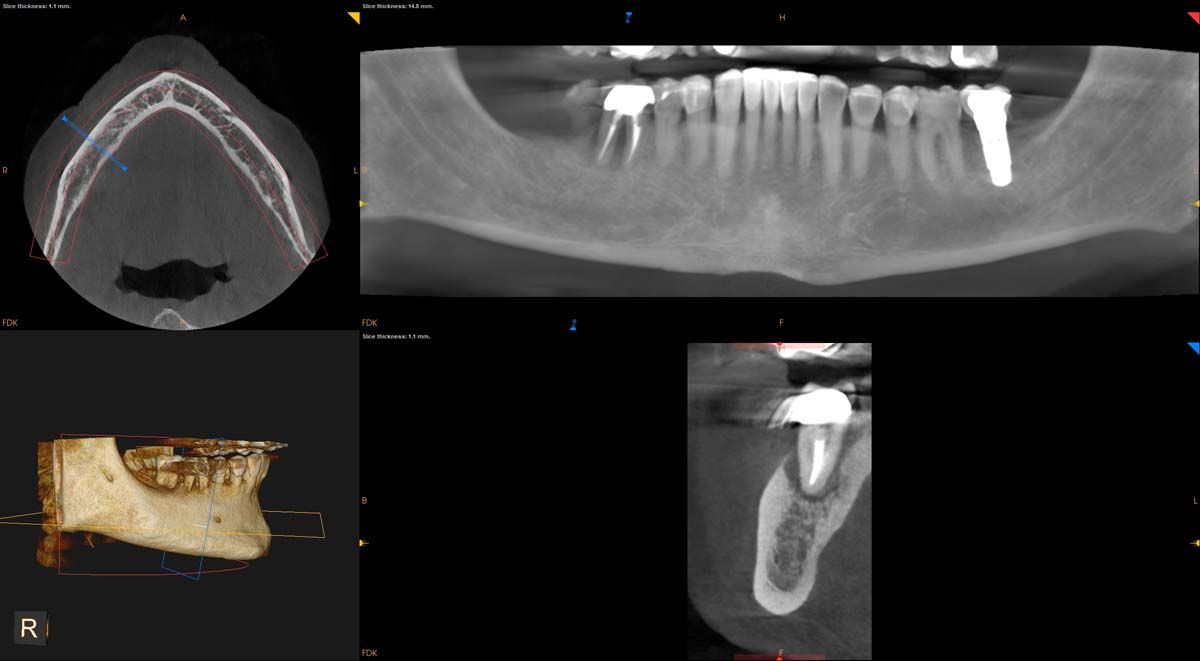

We used to try showing patients their clinical situation on 2D x-rays and demonstrating treatment using models. Later, digital intraoral cameras helped, but they could not show much more than what a patient could see in a mirror. Today, it is possible to show patients every angle of their clinical situation in hyperrealistic 3D with a CBCT scan. Now, when I recommend treatment to patients and they ask why, I am armed with an interactive image captured by my CS 8200 3D extraoral imaging system (Carestream Dental). I scroll through the tooth and bone, point out lesions below the surface, and show why there is or is not enough bone for an implant. If you use something like the Prosthetic-Driven Implant Planning module to automatically merge an intraoral scanner file with the CBCT scan, you create an even more accurate picture. How much easier is it for the patient to accept treatment when they are seeing the end results of that treatment?